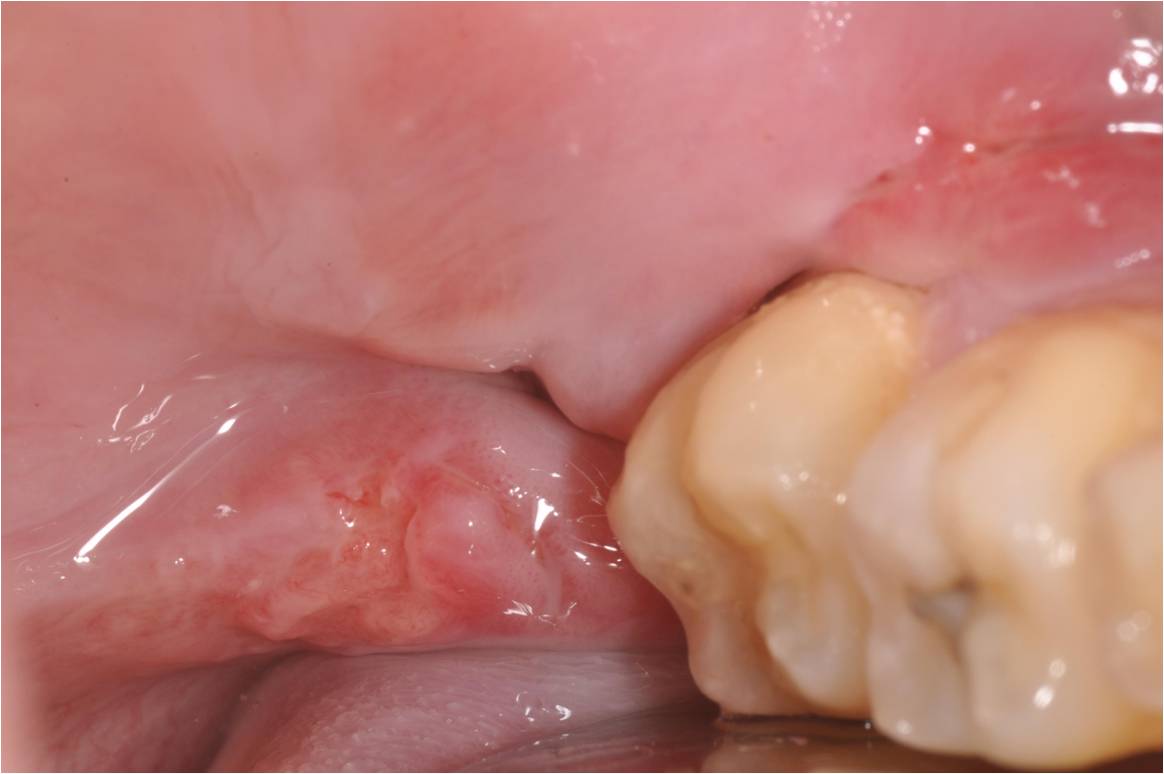

治療前,阻生齒牙齦經常腫脹

術前、術後比較